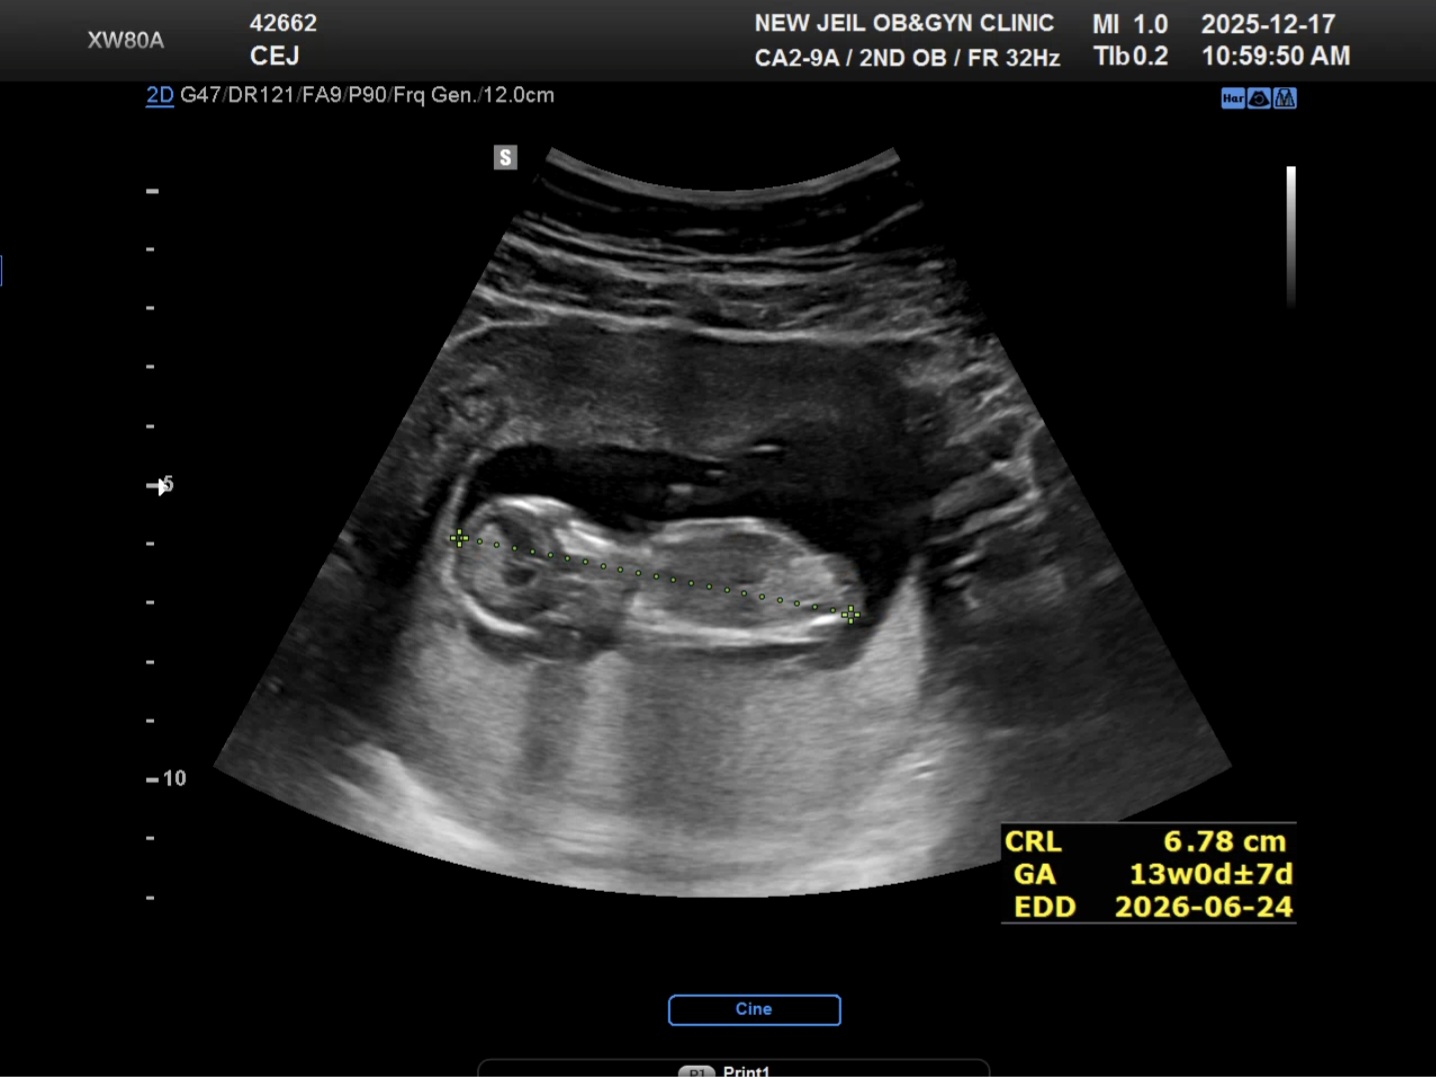

12주차 초음파

주수는 12주차인데 우리 쪼꼬미는 거의 14주 크기이네요 허허허허허 엄마아빠가 커서 아이도 벌써 큰건지..ㅋㅋㅋ 오늘 1차 기형아 검사와 니프티를 했어요 니프티 결과는 더 기다려야하지만 초음파 상의 우리 쪼꼬미는 여아네요ㅎㅎ 여안데 너무 크면 안되는데~걱정걱정😅